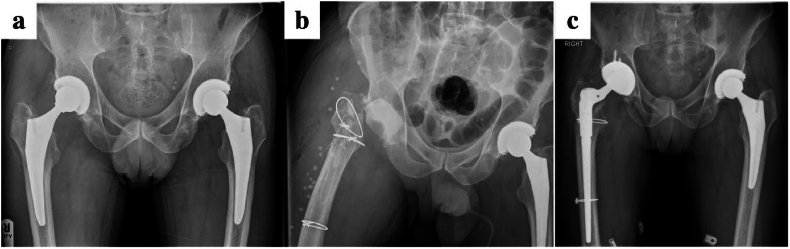

Fig. 4.

Pre and postoperative radiographs of a patient treated for S.aureus periprosthetic infection with a single stage revision. STIMULAN can be seen as a cement restrictor in the intramedullary canal.

Fig. 5.

Radiographs demonstrating delayed-onset right hip PJI due to atypical pathogen (a) treated with two-stage revision. Antibiotic-loaded calcium sulphate beads and a cement block spacer can be appreciated in the first-stage (b) followed by definitive implantation of a cementless revision prosthesis at second-stage (c).